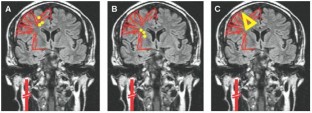

Caplan LR and Hennerici M (1998) Impaired clearance of emboli (washout) is an important link between hypoperfusion, embolism, and ischemic stroke. Arch Neurol 55: 1475–1482

Caplan LR et al. (2006) Is hypoperfusion an important cause of strokes? If so, how? Cerebrovasc Dis 21: 145–153

Sedlaczek O et al. (2005) Impaired washout—embolism and ischemic stroke: further examples and proof of concept. Cerebrovasc Dis 19: 396–401